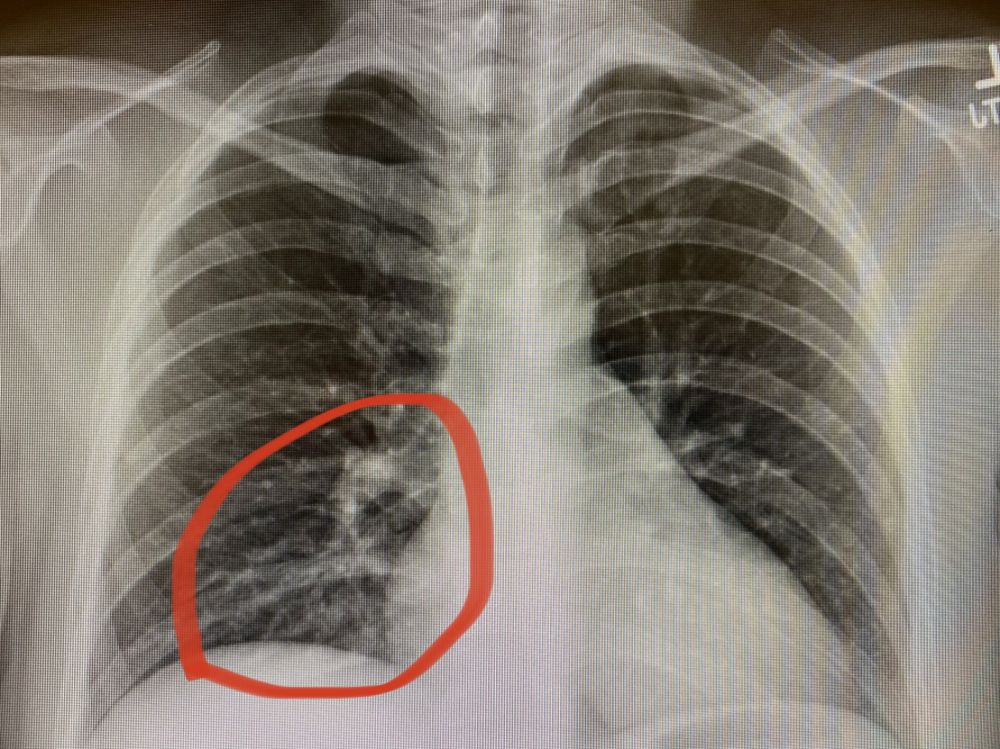

Jones的胸片结果很快回来了:

胸片显示右下肺炎有轻度的浸润病灶

很明显,病人的胸痛和呼吸困难更大的可能是是来自于这个右下叶肺炎,而不是压力和焦虑。虽然是考虑病人新冠肺炎,是病毒感染。但是,临床上我们都给病人用上抗生素:一方面,我们不能完全排除细菌性肺炎;另一方面,即使是病毒性肺炎,后期可能会并发细菌性感染。给病人开了抗生素之后,就建议病人预约新冠检测,并在家隔离。